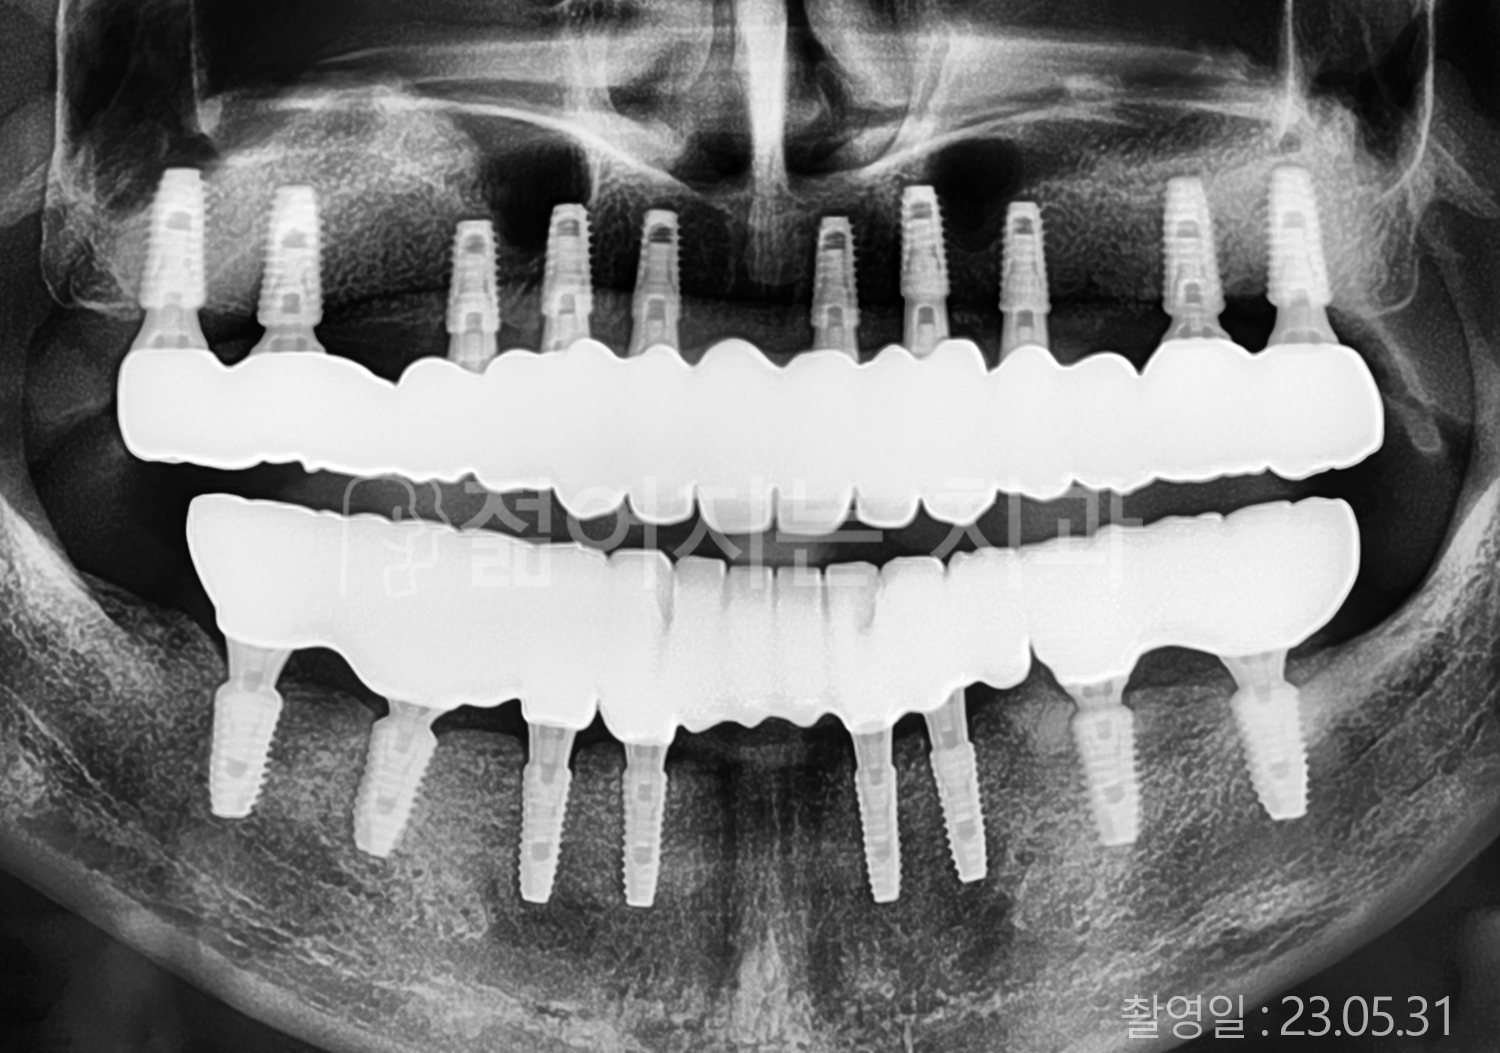

• 70대 고혈압, 당뇨 전체치아 10개 이상 임플란트

• 50대 고혈압, 당뇨 전체치아 10개 이상 임플란트

• 60대 고혈압, 당뇨 전체치아 10개 이상 임플란트

• 50대 전체치아 10개 이상 임플란트

• 70대 당뇨 전체치아 10개 이상 임플란트

• 80대 전체치아 10개 이상 임플란트

• 40대 전체치아 10개 이상 임플란트

• 60대 고협압, 고지혈증 전체치아 10개 이상 임플란트

• 60대 전체치아 10개 이상 임플란트